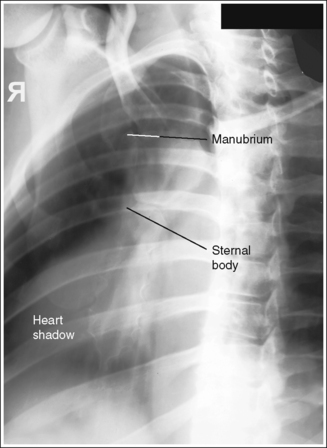

• Importance of choosing the right AP oblique projection (RAO position). The right AP oblique projection (RAO position) is used to rotate the sternum from beneath the thoracic vertebrae. It is chosen over the left anterior oblique (LAO) position because the RAO position superimposes the heart shadow over the sternum (see Image 1). Because the air-filled lungs and heart shadow have different densities, they demonstrate distinctly different degrees of density on an image produced using the same exposure factors. The air-filled lungs demonstrate greater image density than the heart shadow. Positioning the sternum in the heart shadow ensures homogeneous density across the entire sternum. Any portion of the sternum positioned outside the heart shadow demonstrates a darker density than the portion positioned within the heart shadow.

IMAGE 1

The sternum is demonstrated without motion or distortion. The ribs and lung markings are blurred, and the posterior ribs and left scapulae are magnified.

• In the PA oblique projection, the sternum has many overlying structures—the posterior ribs, lung markings, heart shadow, and left inferior scapula. Specific positioning techniques should be followed to show a sharply defined sternum while magnifying and blurring these overlying structures.